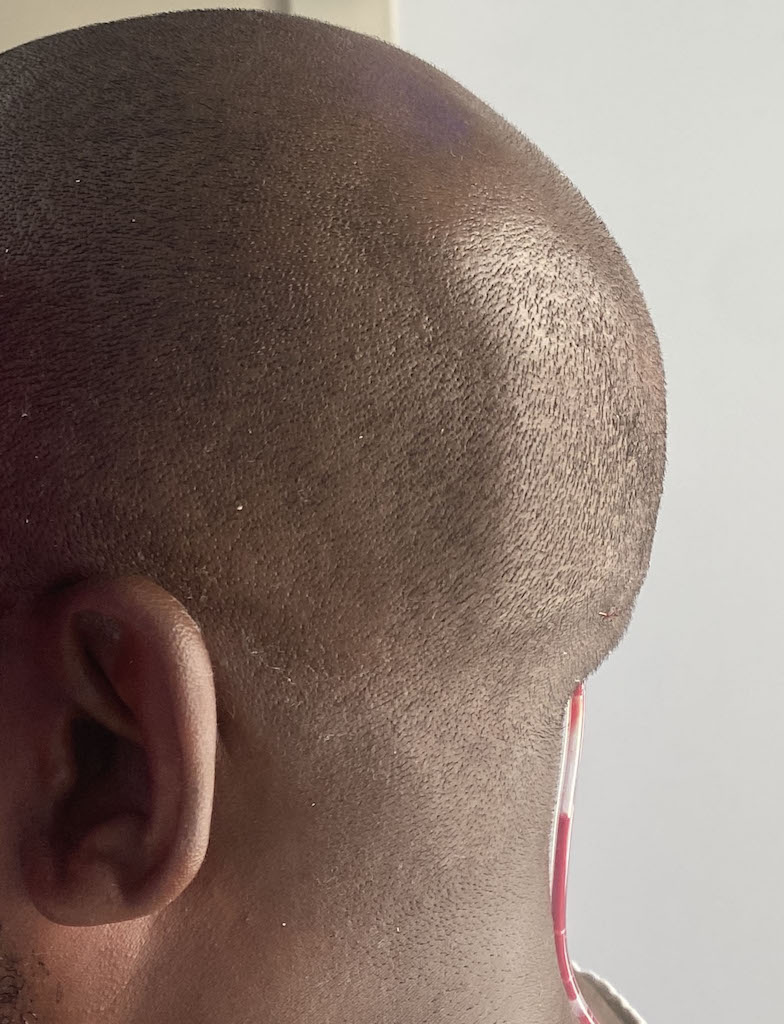

Patient 100

Desire for reshaping of an asymmetric flat back of the head in a shaved head male.

A combined back of the head reshaping procedure was done with a custom skull implant, sagittal ridge reduction and a right temporal muscle reduction.